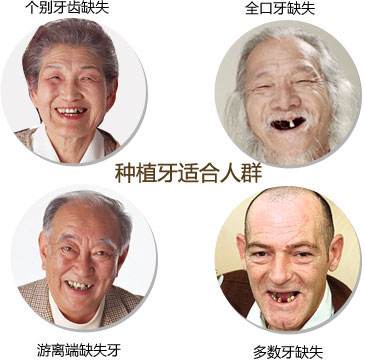

种植牙适合哪些人群?

1、因牙槽骨严重吸收的无牙颌患者;

2、对修复要求较高而常规义齿又无法满足者;

3、因各种原因无法适应可摘义齿者;

4、个别牙缺失,邻牙不宜作基牙或为避免邻牙受损伤者;

5、单个或几个牙缺失,缺失牙前后的牙齿很健康,无龋病、无牙周炎患者;

6、全口牙缺失,采用常规全口义齿很难适应或觉得咀嚼效率不高的患者。 >>>推荐阅读:廊坊市民做种植牙安全吗?